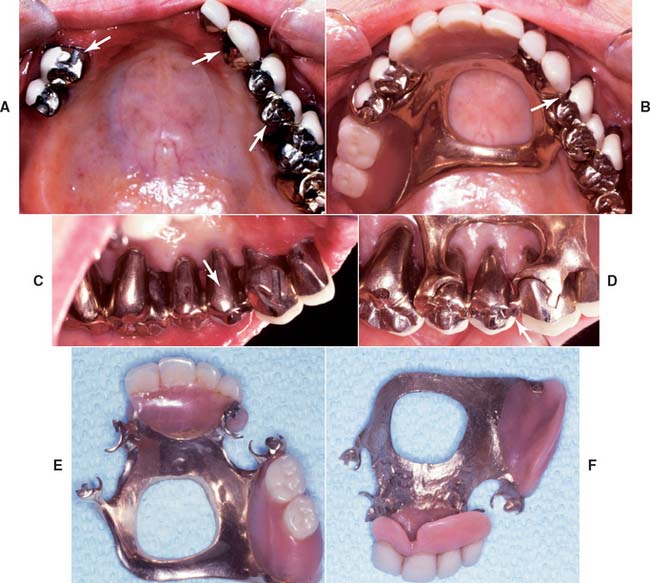

Fig. 32-44 Treatment of a severely periodontally compromised dentition (Treatment XII). A to C, Preoperative photographs. D to F, Fourteen-year postoperative photographs. In the initial discussion of an extensive treatment plan with a patient with a severely compromised dentition, the many risks and possibilities of failure must be fully understood by all parties. This extremely complex rehabilitation continues to serve well today. A meticulous design and frequent recall appointments, combined with outstanding home care, enables this patient to enjoy improved function 14 years later. Throughout the follow-up, the patient was seen at 1-month and periodic 3-month recall appointments, depending on pocket charting and patient motivation. Today, tooth #4 has no attached gingiva and little bone support, but no pocket formation. Initially, it was expected that this tooth would be the first to be lost. In conjunction with loss of tooth #1, this would have necessitated a partial removable dental prosthesis or implant-supported fixed dental prosthesis. Occlusal rests, undercuts, and guide planes had been incorporated in the initial prosthesis to anticipate such failure. After more than 14 years, the prostheses continue to serve satisfactorily. The anterior guidance component is starting to show some wear. Throughout the recall, wherever posterior tooth contact was observed in excursive movements, they were eliminated as part of ongoing occlusal adjustment. Meticulous management of load distribution has contributed to the long-term success of this very complex rehabilitation. G, Preoperative radiographs. H, Fourteen-year postoperative radiographs. This patient was referred initially for complete maxillary and mandibular denture fabrication. Before prosthodontic treatment, the periodontal condition was treated. Treatment included a modified Widman flap, performed throughout both arches. A root resection was done for tooth #14, and tooth #30 was hemisected, which resulted in two premolar-like restorations. Use of the severely tilted tooth #17 as a single abutment to support a very long span posed a substantial risk to the long-term success of this treatment, and the tooth’s future loss was anticipated in the design of the prostheses. Another risk was posed by the root structure of tooth #1, with a small, fused root. This tooth was lost after 14 years as a result of a periodontal defect that progressed along a vertical groove in the fused root.